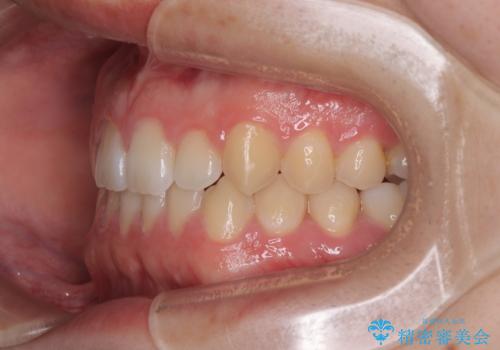

- 「前歯のすきっ歯が気になる」「食べ物が歯の間に詰まりやすい」とのお悩みで来院された20代男性の患者様です。

歯と歯の間に隙間がある**空隙歯列(すきっ歯)**は、見た目の問題だけでなく、食片圧入による歯肉の腫れや、隣接面う蝕のリスク増加につながることがあります。

患者様は「できるだけ目立たない矯正治療」を希望されていたため、インビザラインを用いた治療計画を立案しました。

診査により舌突出癖が認められました。この癖は、すきっ歯の原因となるだけでなく、矯正後の後戻りリスクを高めます。